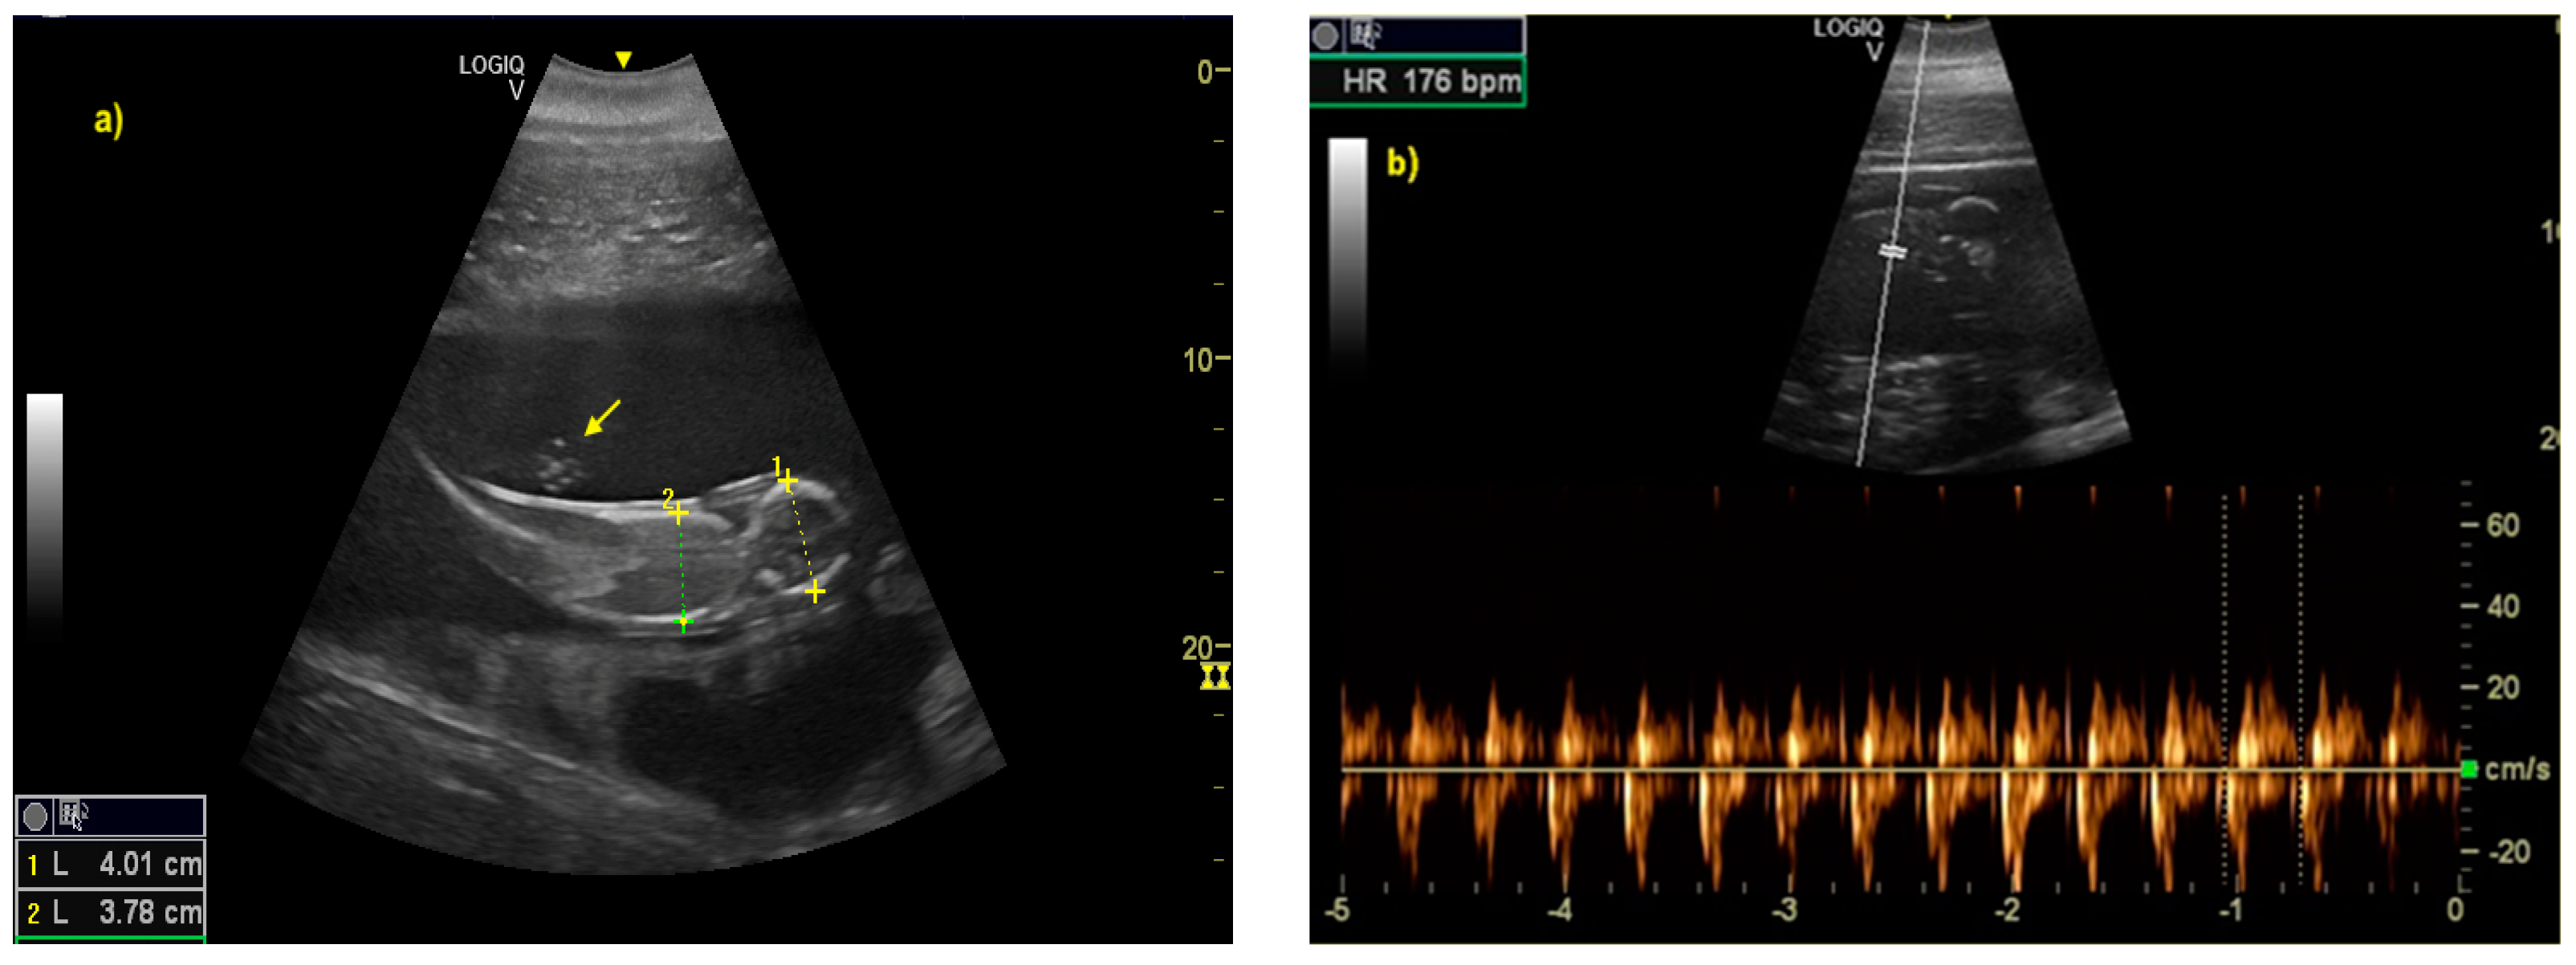

The distinction between head and trunk was visible starting from 68 ± 5 days after ovulation. From the 216 ± 5 days of gestation, measurements started to be hard to realize with accuracy. In fact, in the evaluations after this last period, the position/orientation of the fetus and its size meant that it was not possible to take reliable measurements thereafter. Starting from 68 ± 5 days after ovulation, the embryonic cardiac mechanisms were displayed as a point of maximum fluctuation of the echoes. The heart rate was measured because the cardiac mechanics became visible and remained constant between 155 and 198 bpm until the ninth month of pregnancy (Figure 3). During the last 3 months, it stabilized at 140 bpm, to reach 85 ± 5 bpm in the last 2 weeks of gestation. The first abdominal organs to be visualized were the stomach and the urinary bladder (98 ± 3 and 110 ± 2 days of gestation, respectively), which appeared as distinct and anechoic cavities. It was also possible to recognize the eye as an anechoic cavitary structure (Figure 4).

Figure 3.

(a) The distinction between head and trunk was clear between 68 ± 5, up to the 216 ± 5 day of gestation. It allowed measurement of bi-parietal diameters. The umbilical cord was already easy guessed (as indicated by yellow arrow). (b) The fetal heart rate (HR) was measured once the cardiac mechanics became visible.